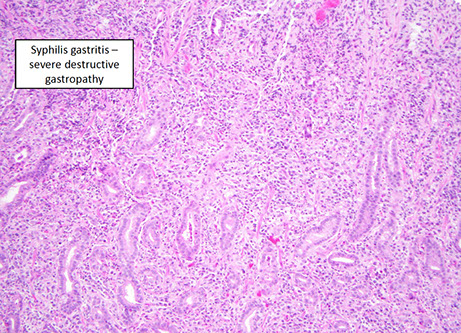

Infectious gastritis (syphilis, CMV, EBV)

- eos may be prominent, but not usually counted

Syphilis

- has a variable appearance, having lots of mixed inflam (similar to autoimmune pangastritis) c gastric gland damage; should do direct IF or immunolabeling if suspected

CMV

not uncommon in inpts, may be mistaken for lymphoma

EBV

- can appear similar to large cell lymphoma in same way that infectious mono simulates leukemia

EBV gastritis - mimics lymphoma [1]